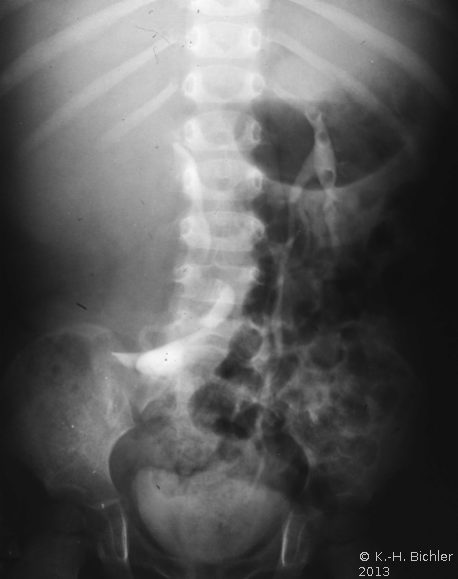

Die abdominale Sonographie bzw. die Computertomographie haben die Ausscheidungsurographie als die bildgebende Untersuchungstechnik bei Patienten mit Oberbauchtumor, z.B. Wilmstumor, verdrängt. Einige Ausscheidungsurographien von Kindern mit Wilmstumoren aus unserer Sammlung aus den 70er Jahren des vergangenen Jahrhunderts sind aus didaktischen Gründen hier wiedergegeben. Die Bilder zeigen instruktiv die Größe und Verdrängung durch den Tumor (

4 Abbildungen HG1).